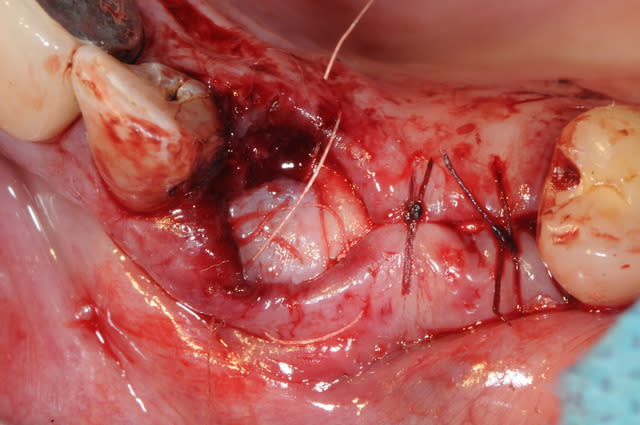

je prélève un petit lambeau au palais, l'incision se fait à l'opposé du centre du greffon de façon à avoir un biseau partout.

je passe un fil de suture avant de suturer. c'est trop difficile de travailler un truc fin comme du papier.

je replace le greffon au dessus de la membrane et il vient tout naturellement se plaquer à celle ci.

je précise que c'est un fil de suture avec une aiguille à chaque extrémité du fil.